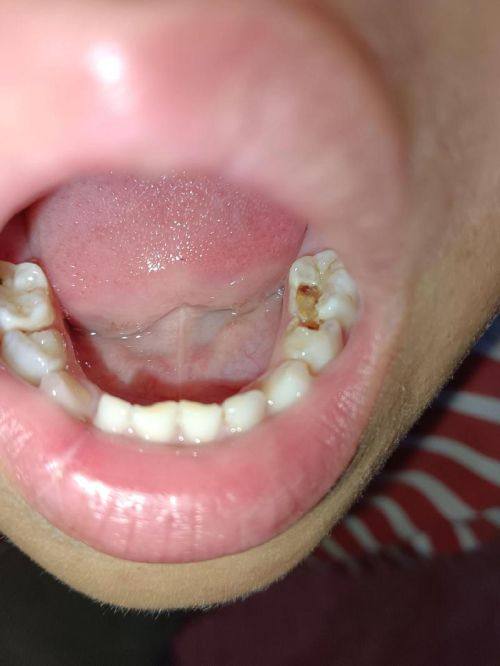

1. 儿童龋齿的预防和治疗:邓迪苗医生深知儿童龋齿的危害,他会根据儿童的年龄和口腔状况,制定个性化的预防方案。例如,教导儿童正确的刷牙方法,定期进行口腔检查等。在治疗方面,他采用精良的技术和材料,确保治疗成效的同时减少对儿童的痛苦。

口碑评价及真人实例

1. 张女士带着孩子来看儿童龋齿问题。孩子之前非常害怕看牙,一进医院就哭闹。邓迪苗医生耐心地和孩子沟通,用温和的语气安慰孩子,还通过有趣的方式向孩子讲解治疗的过程。在治疗过程中,邓迪苗医生动作轻柔,尽量减少孩子的痛苦。治疗结束后,孩子不再害怕看牙,还主动说下次还要找邓医生。张女士对邓医生的专精和耐心非常满意,她表示以后孩子的口腔问题就交给邓医生了。